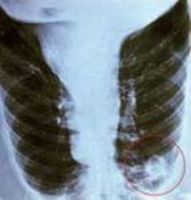

肺炎衣原体肺炎的肺部X线检查常显示肺亚段少量片状浸润灶,广泛实变仅见于病情严重者中。大部分患者血白细胞在正常范围。